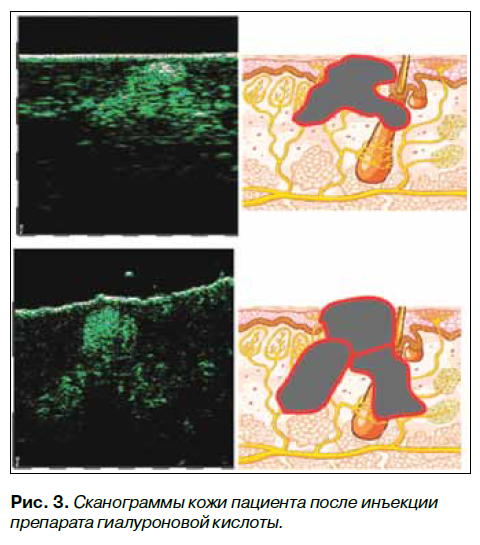

При ультрасонографии кожи в области носогубных складок (Рис. 3) были выявлены участки повышенной акустической плотности 78–90 ед (в контроле 22–14 ед), которые представляли собой интрадермальные сферические очаги 500–800 мк, и тяжи длинной 1,5–2,5 мм, диаметром 700–900 мкм, расположенные в преимущественно в верхних и средних слоях дермы. Со слов пациентки, 10 лет назад ей была сделана инъекция препарата биодеградируемой гиалуроновой кислоты. По данным литературы и информации производителей препараты стабилизированной гиалуроновой кислоты

должны рассасываться в течение 6–18 месяцев [2], однако даже 10 лет спустя мы наблюдаем определенные морфологические изменения по типу микросклерозирования.

Сверху вниз расположена сканы 22 и 75 МГц, кожи правой носогубной складки. Справа от каждого скана размещена микроанатомическая схема, демонстрирующая локализацию патологического процесса, его глубину и границы.